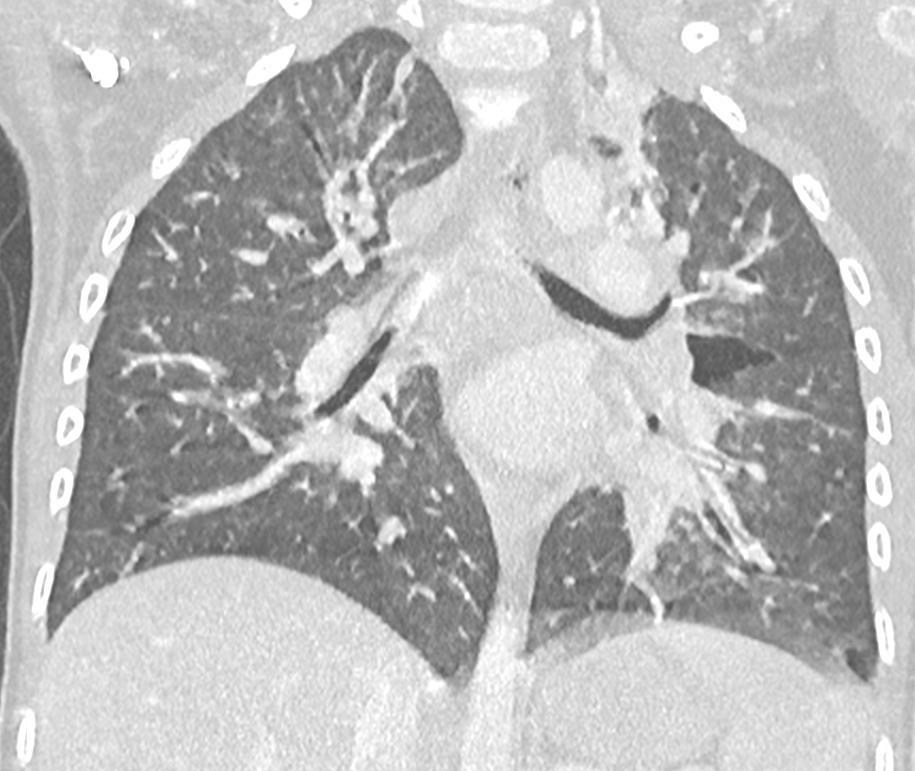

Acute Pediatric COVID-19: CT

21 Imaging of Covid 19 infection in children

3 Phases

Early: "Halo" sign

Local infection

Progressive: Diffuse GGO

Developed: Consolidation

Surr vasc congestion

Inflammation - adj alveoli

Alveoli fill with fluid/cells

Imaging of Covid 19 infection in children

Local infection Surr vasc congestion